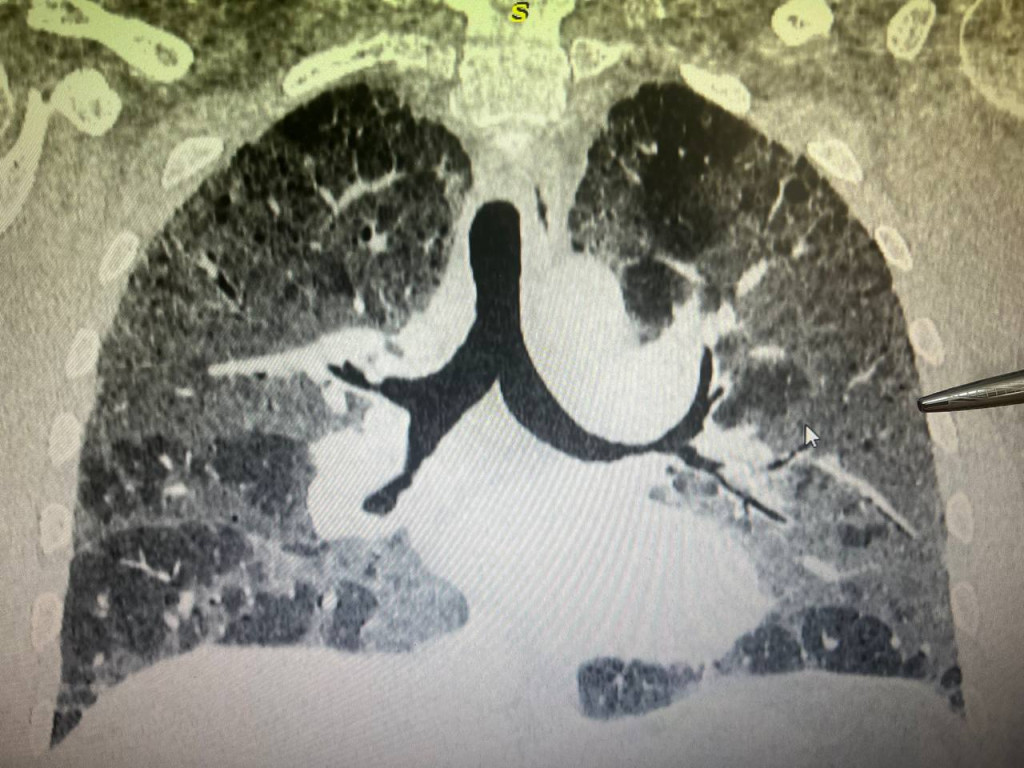

Интерстициальные Заболевания Легких: Симптомы и Лечение